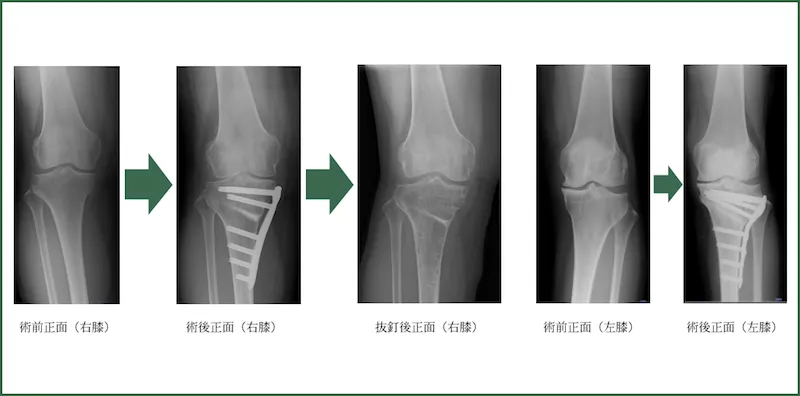

脛骨高位骨切り術

(HTO: High tibial osteotomy)

脛骨(スネの骨)を内側から骨切りを行い、内側を開大して人工骨を充填し、プレートで固定する方法です。体重の荷重軸は通常内側を通るのですが、変形性膝関節症(内側型)では極度に内側荷重となっています。その荷重軸をやや外側に移動させる手術です。

当院での主たる適応は、可動域がほぼ保たれているスポーツを行う70歳までの方です。特にマラソンなどの趣味がある方はよい適応となります。ほかにも適応の条件はいくつもありますが、診察時に説明いたします。ただし、骨切り術のみでなく、半月板縫合や修復術を追加することが多いです。

手術時間:平均75分(これに難易度の高い半月板縫合術も追加するのでプラス90分程度)

出血量:50ml程度

年間件数:70件程度(2023年)

*膝周囲骨切り術として大腿骨遠位骨切り術(DFO)やDouble level osteotomy(DLO)も行っている